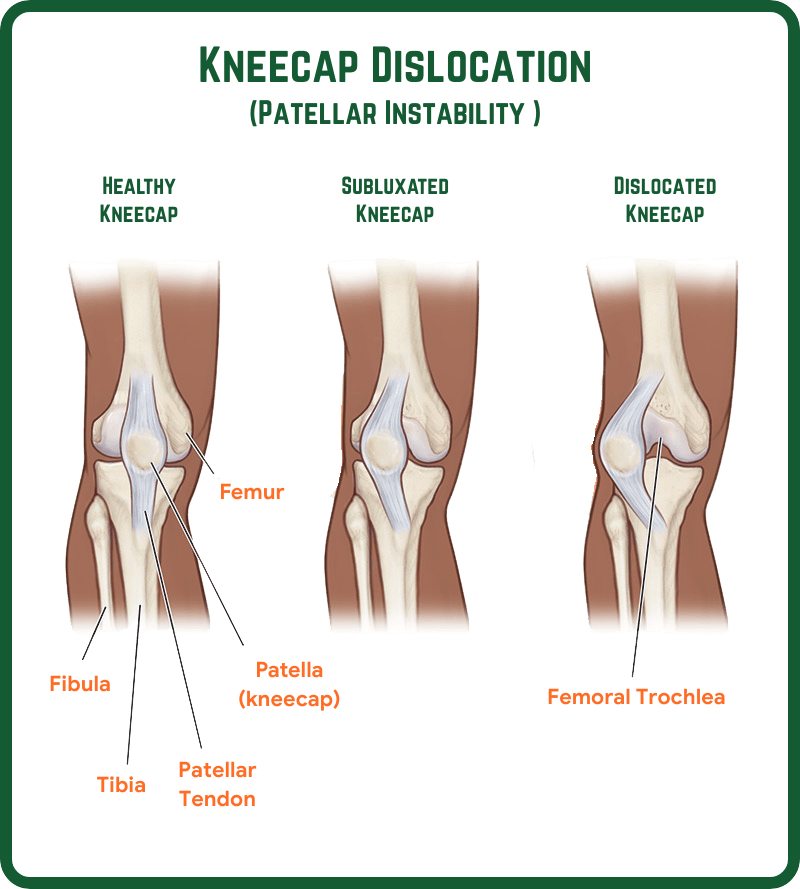

What is Patellar Instability (Kneecap Dislocation)?

Patellar instability often known as kneecap dislocation occurs when the patella (kneecap) slips out of its normal groove in the thigh bone (femur).

Patella normally glides smoothly in the groove of the thigh bone (femur), this grove is called trochlea. However, occasionally it may not glide smoothly in the groove (Mal-tracking) leading to patellar instability and worst-case scenario, the patella can dislocate leading to pain and instability